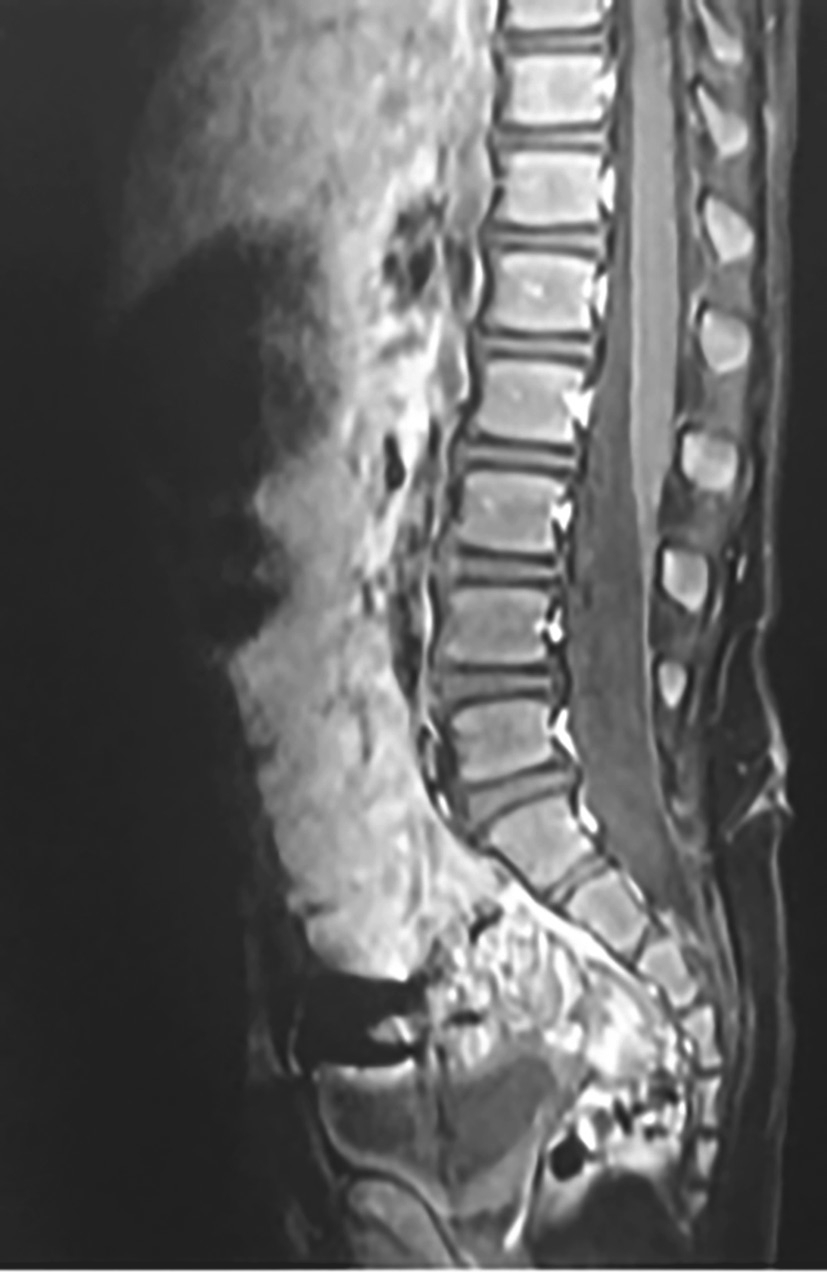

辅助检查:MRI(图4-1-6)示脊柱裂伴脊膜膨出、脊髓栓系低位。CT(图4-1-7)示S 1 、S 3 ~S 5 骶椎裂,伴骶尾部脊膜膨出;脊髓栓系低位可能。

图4-1-6 MRI图像

现病史:患儿半年前开始逐渐出现跛行,逐渐加重,伴便秘,大便每3~4日1次。小便有力,无漏尿、失禁等。就诊于医院神经外科门诊,行MRI(图4-1-8)提示脊髓栓系,收入院。

图4-1-8 患者MRI图像

辅助检查:MRI提示骶椎裂,圆锥位于L 3 水平。